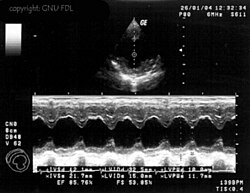

M-Mode

Eine weitere häufig eingesetzte Darstellungsform ist der M- oder TM-Mode (englisch für (time) motion). Dabei wird ein Strahl bei einer hohen Impulswiederholungsfrequenz (1 – 5 kHz) eingesetzt. Die Amplitude des Signals wird auf der vertikalen Achse dargestellt; die von den hintereinander liegenden Impulsen erzeugten Echozüge sind auf der horizontalen Achse gegeneinander verschoben. Diese Achse stellt also die Zeitachse dar.

Bewegungen des Gewebes bzw. der untersuchten Strukturen haben Unterschiede in den einzelnen Impulsechos zur Folge, es lassen sich Bewegungsabläufe von Organen eindimensional darstellen. Die M-Mode-Darstellung ist häufig mit dem B- bzw. 2D-Mode gekoppelt.

Ihre Hauptanwendung findet diese Untersuchungsmethode in der Echokardiografie, um Bewegungen einzelner Herzmuskelbereiche und der Herzklappen genauer untersuchen zu können. Die zeitliche Auflösung dieses Modus ist bestimmt durch die maximale Wiederholrate der Schallimpulse und beträgt schon bei 20 cm Tiefe über 3 kHz.